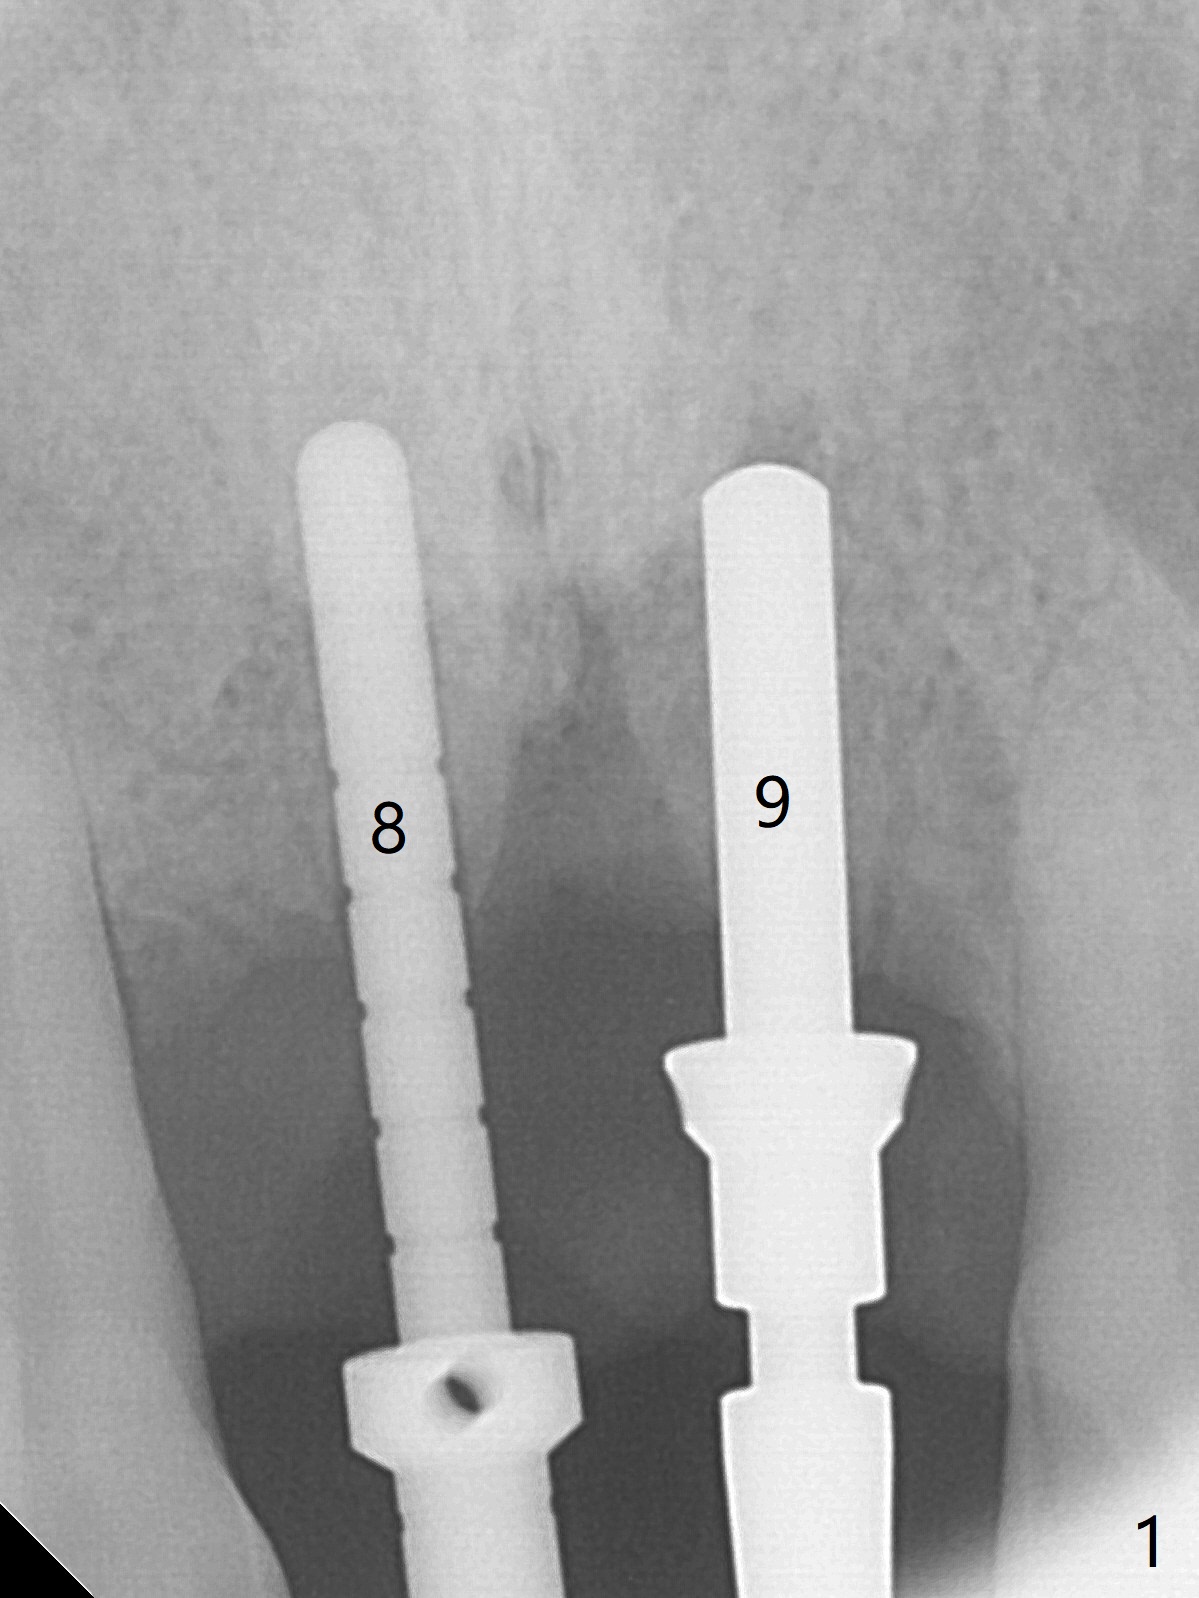

There is no buccal plate at #8 or 9 when the teeth are extracted as well as severe soft tissue defect at #8. Osteotomy is initiated as palatal as possible (Fig.1). When 3.5x13 mm implants are placed initially, the one at #8 is supracrestal (Fig.2 ^). To reduce the chance of peri-implantitis, the implant is placed deeper (Fig.3 (~2 mm implant threads exposed buccally)) with placement of sticky bone around the implants and 4.5x5.5(4) mm abutments (Fig.3 *). The buccal soft tissue defect #8 is repaired with a piece of PRF membrane (Fig.4 *), followed by periodontal dressing. Smaller 2-piece implants (3 mm, IBS) with smaller abutments (4 mm) may further reduce chance of periimplantitis and easy buccopalatal reduction of the abutments for restoration. The periodontal dressing remains stable 7 days postop (Fig.5) because it wraps around the abutments (Fig.6 A). By the time the periodontal dressing gets loose, #8 buccal soft tissue defect should be healing. When breaking-down periodontal dressing is removed 17 days postop, the coronal abutments and bone graft are exposed; after fabrication of provisional crowns (Fig.7), periodontal dressing is re-applied buccally. When the second dressing dislodges 5 weeks postop, the buccal soft tissue appears to reduce (Fig.8). Raising flaps may be less traumatic. A piece of bone graft is being extruded 4 months postop (Fig.9 >). After the abutments change from 4.5x5.5(4) to 4.5x7(3) mm, new temporary crowns are fabricated (Fig.10 (4.5 months postop)). CT shows apparent buccal bone at #8 and 9 (Fig.11,12). How to improve cosmetic?